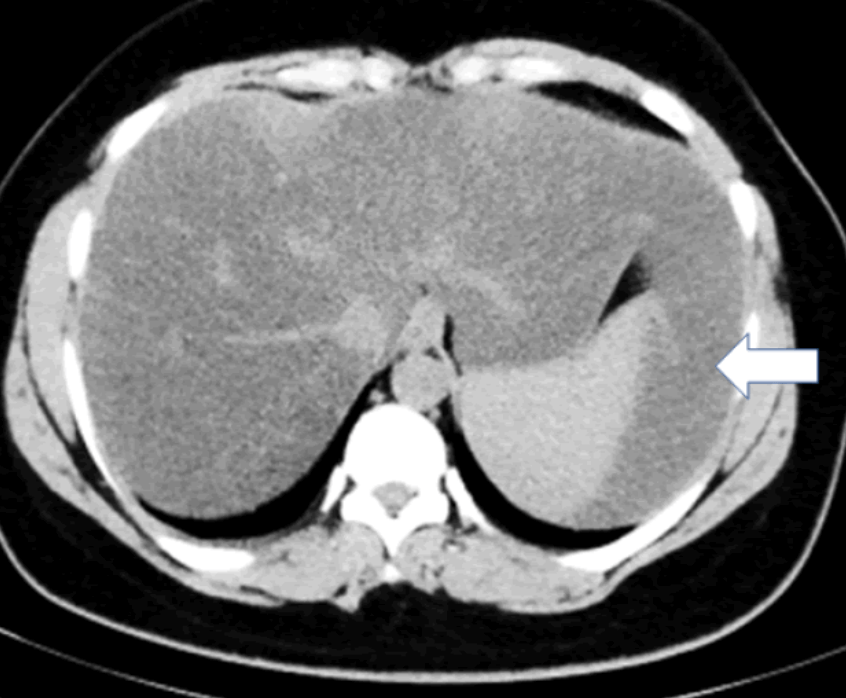

2. Long left lobe of the liver = Beaver tail liver

Beaver tail liver 좌엽이 길고 커져서 비장에 인접해 있다. 마치 비장의 피막하 혈종(subcapsular hematoma)처럼 보인다. 주로 마른 여자에서 확인된다.